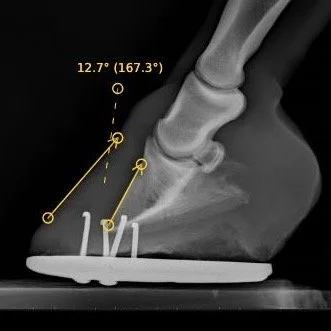

Laminitis with rotation